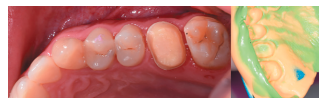

En la Historia Clínica no se evidenciaron antecedentes médico-quirúrgicos de interés, alergias medicamentosas conocidas ni hábitos nocivos. En la exploración extraoral no se apreciaron datos relevantes. En la exploración intraoral se apreciaron dientes no restaurables en posición de 2.6 y 4.6 y la presencia de los terceros molares inferiores retenidos. (Figuras 1 y 2).

En la exploración radiográfica, mediante radiografía panorámica, se apreciaron ambos terceros molares inferiores retenidos, en posición horizontal (Figura 3), e imágenes radiolúcidas apicales en posición de 2.6 y 4.6. En el escáner de haz cónico se evaluó la morfología radicular del tercer molar superior izquierdo, y la dimensión de la lesión radiolúcida apical del primer molar superior izquierdo (Figura 4), datos necesarios para valorar el grado de adaptación del diente donante en el lecho receptor.

Se planificó la exodoncia del 4.6 y 2.6, y el legrado de los procesos apicales, y se le sugirió al paciente el autotrasplante del tercer molar superior izquierdo (2.8) para sustituir el 2.6 (Figura 5).